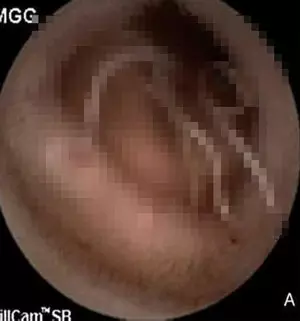

이후 캡슐내시경을 시행한 결과, 기생충이 소장 점막에 달라붙은 것을 확인했다. 캡슐내시경은 알약처럼 생긴 작은 카메라를 삼켜 위장관, 특히 소장을 촬영하는 검사 방법이다. 기생충이 피를 빨아먹으면서 궤양과 출혈을 일으킨 것이다.